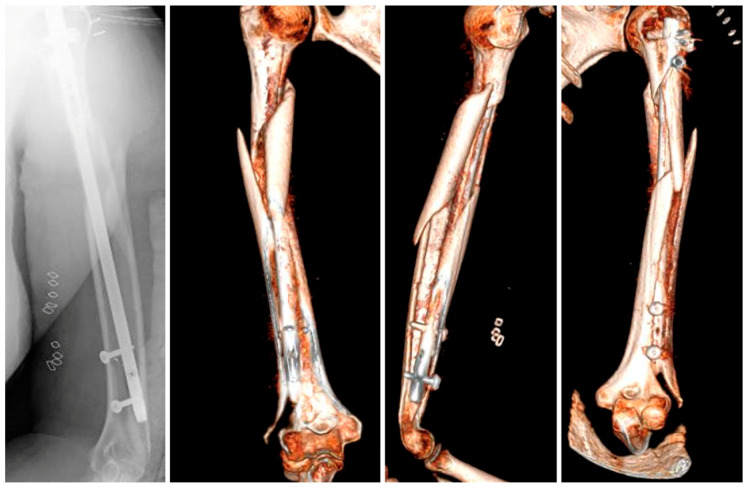

背景和临床意义:非假体种植体周围骨折(NPPIFs)是发生在内固定装置周围的罕见损伤,与假体周围骨折不同。虽然大多数研究集中在股骨,但肱骨nppif的文献记录很少。本病例说明了复杂的肱骨NPPIF,并强调了关键的手术注意事项。病例介绍:一名62岁女性在跌倒后出现螺旋状肱骨轴骨折(ao12b2)。在闭合复位和顺行髓内钉固定后,术中远端联锁螺钉发生种植体周围骨折。CT显示一复杂骨折,从外侧髁延伸至肱骨近端。治疗包括植入物移除和切开复位双钢板固定-外侧远端和螺旋形近端钢板-加上环扎带和载抗生素珠。恢复顺利,6个月时实现了全范围活动。一年后,DASH评分和MEPS分别为86分和75分。结论:肱骨nppif具有挑战性,需要个性化的、生物力学健全的策略。这个病例强调了术中评估和谨慎选择植入物在肱骨骨折治疗中的重要性。

Background and Clinical Significance: Non-prosthetic peri-implant fractures (NPPIFs) are rare injuries occurring around internal fixation devices, and are distinct from periprosthetic fractures. While most studies focus on the femur, humeral NPPIFs remain poorly documented. This case illustrates a complex humeral NPPIF and highlights key surgical considerations. Case Presentation: A 62-year-old woman presented with a spiral humeral shaft fracture (AO 12B2) after a fall. Following closed reduction and antegrade intramedullary nailing, an intraoperative peri-implant fracture occurred at the distal interlocking screw. CT imaging revealed a complex fracture extending from the lateral condyle to the proximal humerus. Treatment included implant removal and open reduction with dual plate fixation-lateral distal and helically contoured proximal plates-plus cerclage bands and antibiotic-loaded beads. Recovery was uneventful, with a full range of motion achieved at six months. At one year, the DASH score and MEPS were 86 and 75, respectively. Conclusions: Humeral NPPIFs are challenging and require individualized, biomechanically sound strategies. This case reinforces the importance of intraoperative assessment and careful implant selection in humeral fracture management.